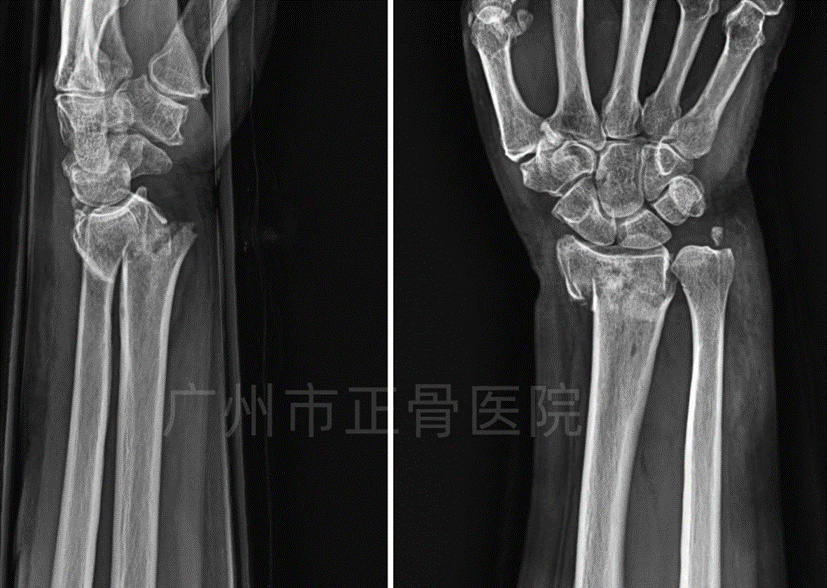

X线片检查结果:“左侧桡骨远端粉碎性骨折,骨折远端向背侧移位,向掌侧成角,断端嵌插短缩,尺骨茎突骨折,下尺桡关节位置欠佳。”

诊断:左桡骨远端粉碎性骨折合并尺骨茎突骨折、下尺桡关节半脱位。

▲复位前,骨折短缩、成角移位